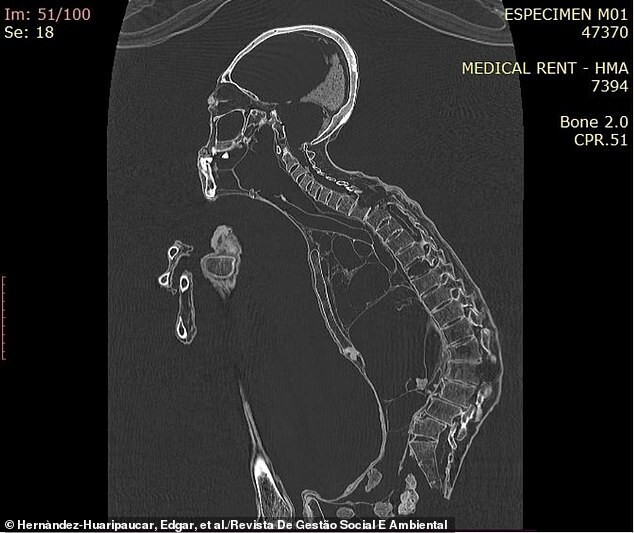

However, recent analysis of one of the humanoids, designated "Maria" (M01), showed surprising results. Peruvian scientists carried out a series of tests, including electron microscopy, x-rays and scanning of internal organs.

The study showed that Maria has certain biological similarities with humans. Her bones blend smoothly under a mummified shell, like those of humans, and her elongated skull shows no signs of artificial deformation.

“The most striking feature of the skull is its significant elongation, with no outward signs of compression of the skull by external agents,” says the study, published in the Journal of Social and Environmental Management. “In particular, it is the cranial vault that demonstrates atypical growth and development, reminiscent of the dolichocephalic phenotype. In addition, the cranial volume is 30 percent larger than that of a normal person."

Maria also exhibits marked morphological and anatomical differences from humans. She lacks hair and external ears, and her hands and feet have three fingers with four phalanges each. She also has bulging eyes, protruding jaws, and six missing teeth.

“The most striking and unusual features of the humanoid body are in its arms and legs,” the scientists note. “The arms are as wide as a man’s, but eight inches longer.” It is noteworthy that each finger of the hand has four phalanges, unlike the three phalanges of an ordinary person. The bones of the foot flow smoothly into three toes, the width of which is similar to the width of the human foot, but they are much longer - nine inches. At the level of the toes, four phalanges are observed on each of the three feet, while normal people usually have only three phalanges per toe."

Compared to a normal human foot, Mary's calcaneus, which forms the heel, has a different shape and structure. Typically, human heel bones have a large bump at the back that helps support body weight and maintain balance when a person stands upright on two legs. However, Maria does not have this tubercle, which suggests that she walked hunched over to maintain stability.

Analysis of the images also showed that the creature suffered from arthritis in its arms and legs, and also had a damaged spine.